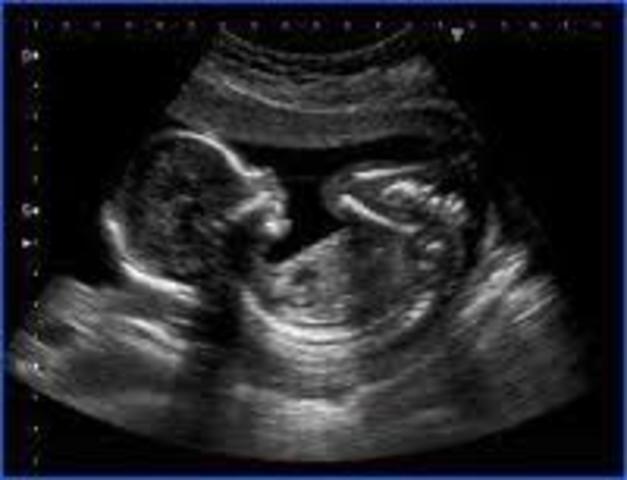

Los principales rasgos externos de esta semana es el desarrollo del cuello y la barbilla separado del torax, el corion se divide en corion leve y frondoso, los parpados se juntas y se fusionan, los genitales externos comienzan a ser específicos y ya hay deglucioó del liquido amniótico.

Dentro de los rasgos internos esta que se producen los primeros movimientos musculares, la hipófisis produce ACTH y gonadotropina y se completan las válvulas semilunares del corazón.